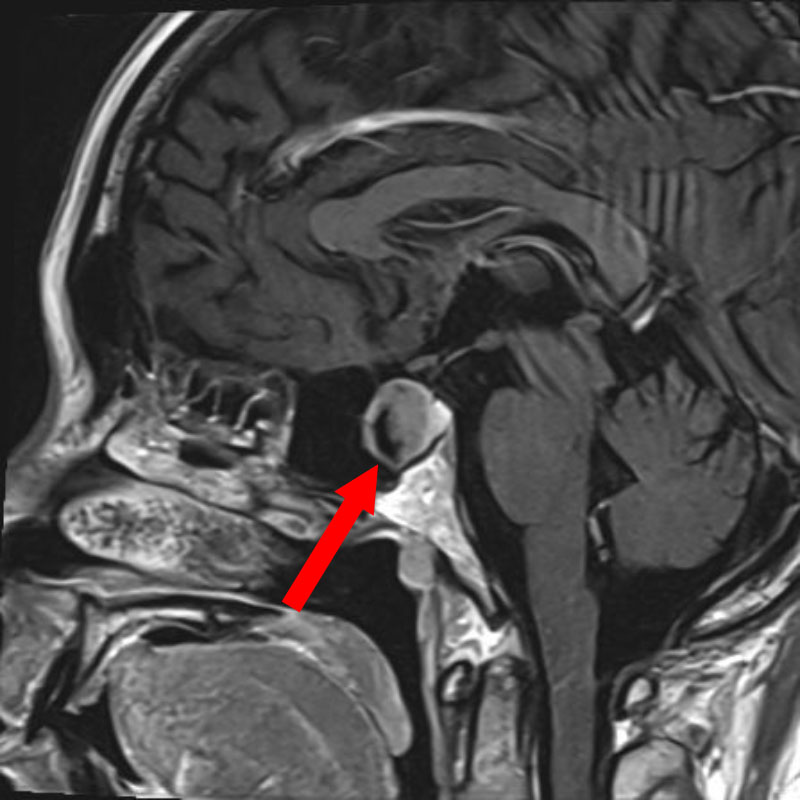

頭蓋咽頭腫

頭蓋内腫瘍摘出術

No.’25_96 手術前1

No.’25_96 手術前2

No.’25_96 摘出 前

No.’25_96  摘出 中

No.’25_96 摘出 後